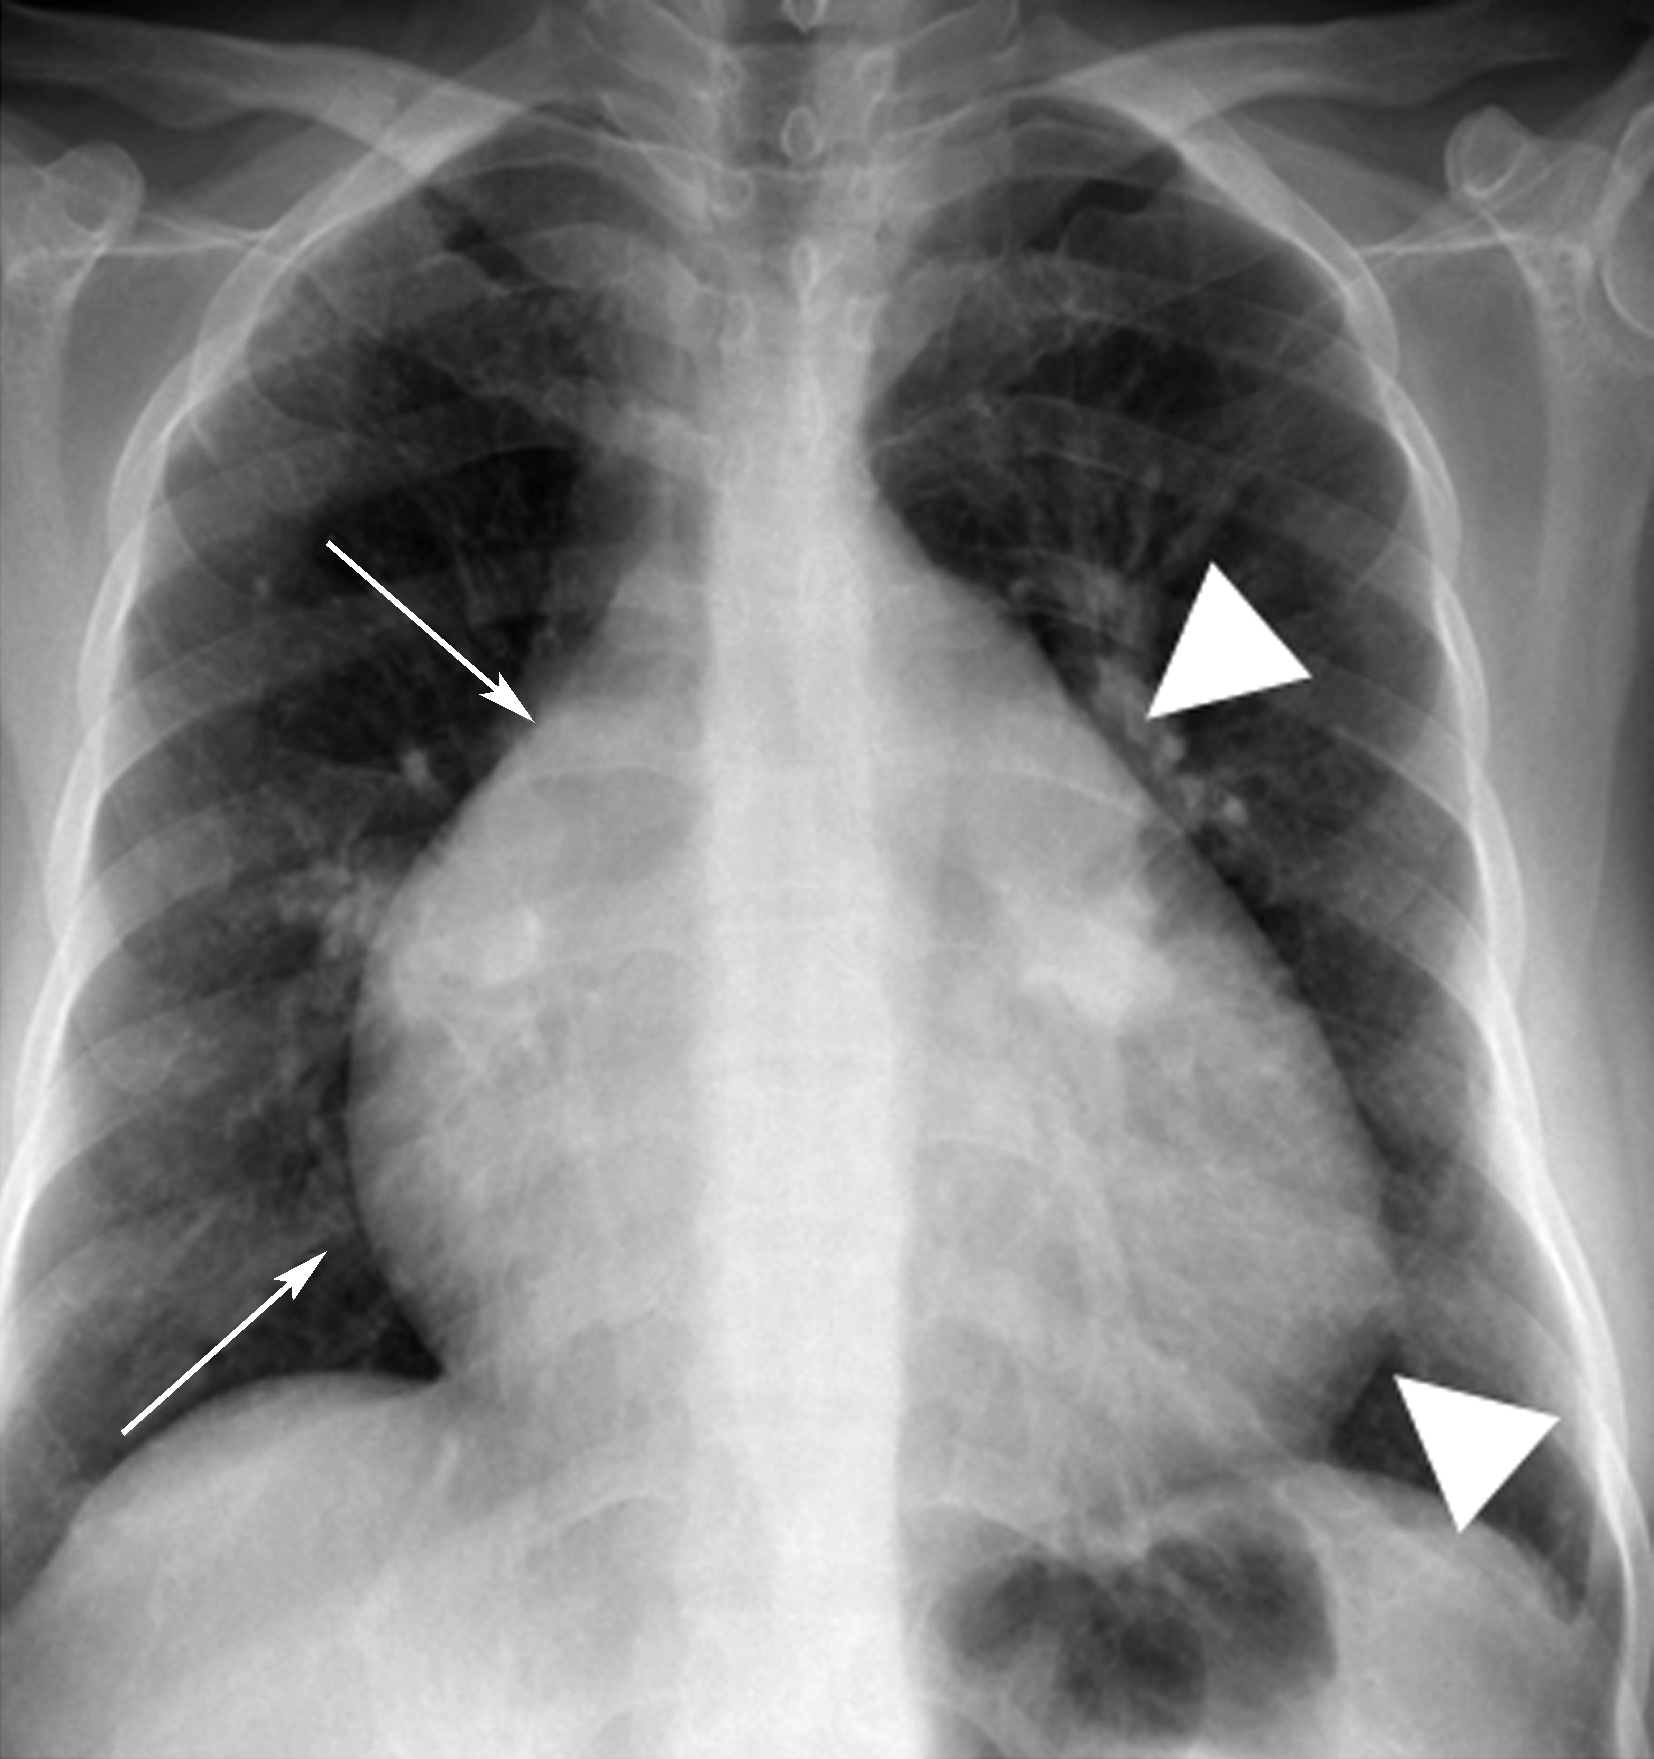

图7-2-9胸部正、侧位X线片示:两肺血多,肺动脉段凸,右下肺动脉增宽>1.5cm;右心室增大(肥厚为主)。X线片诊断:肺动脉高压,继发于左-右分流先天性心脏病。CTA证实为房间隔缺损(Ⅱ孔型)。

图7-2-9 男,39岁,劳累后气短,心电图:右心室肥厚;超声心动图:肺动脉高压,72mmHg